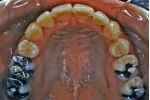

| マルチブラケット終了時

|